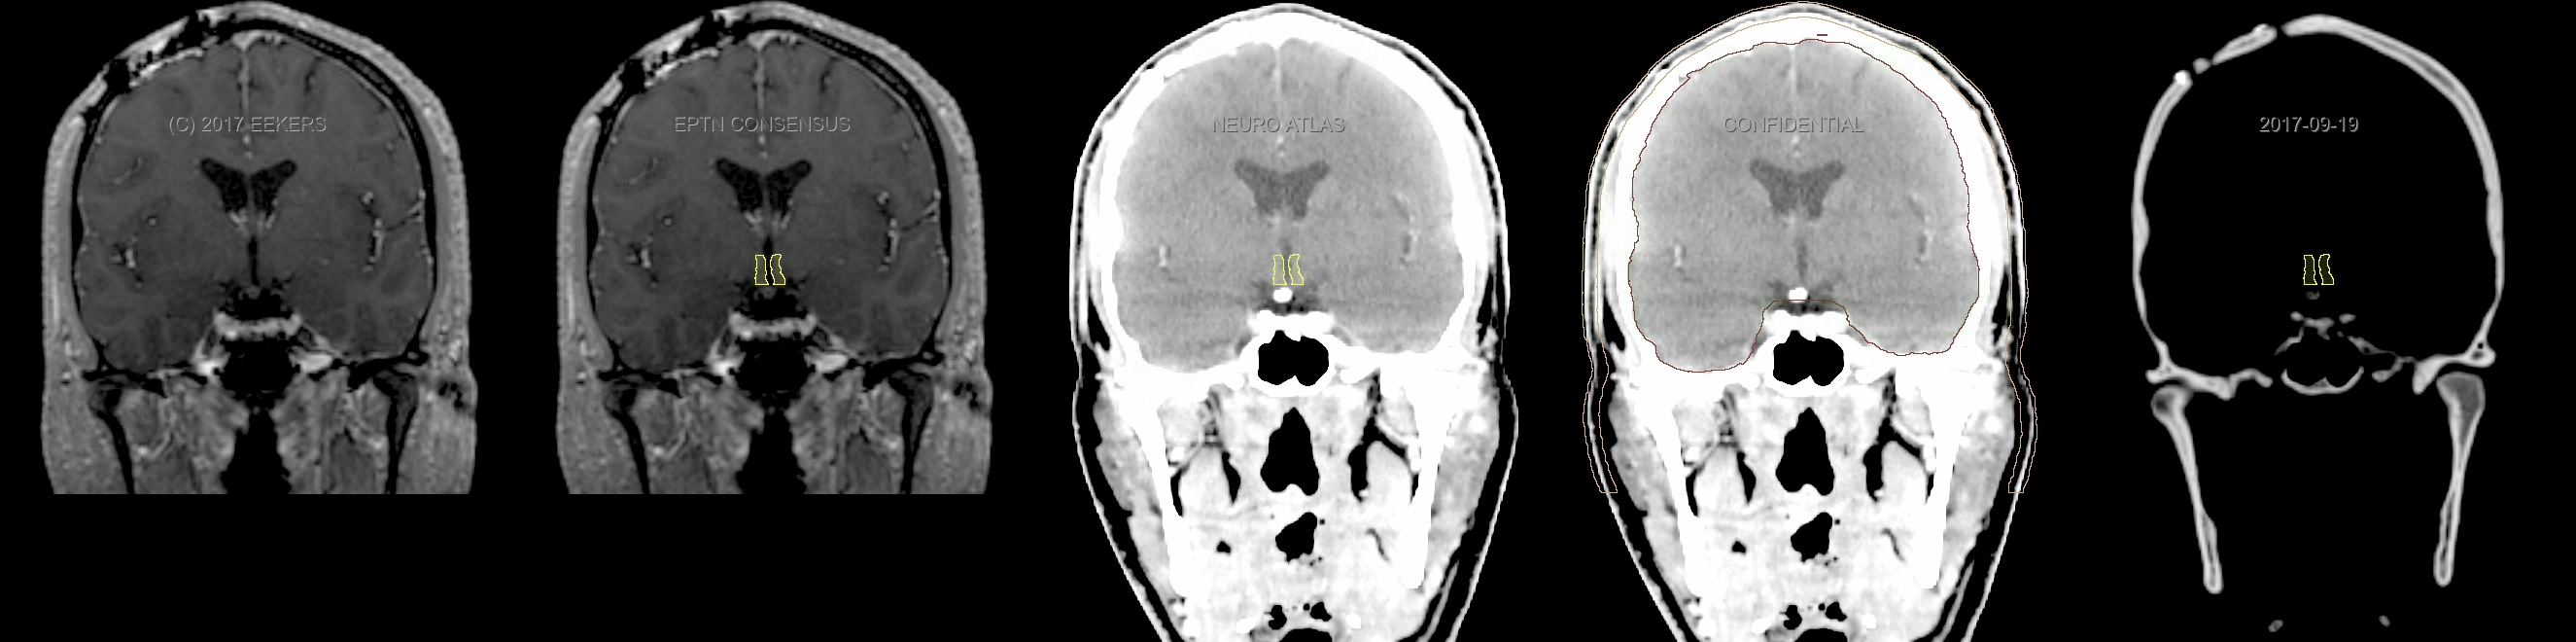

Eekers et al. have published an international neurological atlas for contouring of organs at risk in consensus with the European Particle Therapy Network (EPTN). The purpose of this consensus atlas is to decrease inter- and intra-observer variability in delineating OARs relevant for neuro-oncology. We propose this atlas is used in photon and particle therapy in order to derive consistent dosimetric data. When required this atlas will be updated according to new insights.

Included are all OARs known to be relevant for radiation-induced toxicity in neuro-oncology: brain, brainstem, cochlea, vestibulum & semicircular canals, cornea, lens, retina, lacrimal gland, optic nerve, chiasm, pituitary, hippocampus and skin. A new OAR relevant for neuro-cognition, the posterior cerebellum is also included.

Three-dimensional delineation of the fifteen consensus OARs for neuro-oncology are shown on CT and 3 Tesla (3T) MR images (slice thickness 1 mm with intravenous contrast agent). All are presented in transversal, sagittal and coronal view.

From left to right: MR without structures, MR with structures, CT (WW/WL 120/40) with structures, CT (WW/WL 120/40) with Brain and Brainstem Surface, CT (WW/WL 1500/120)with structures